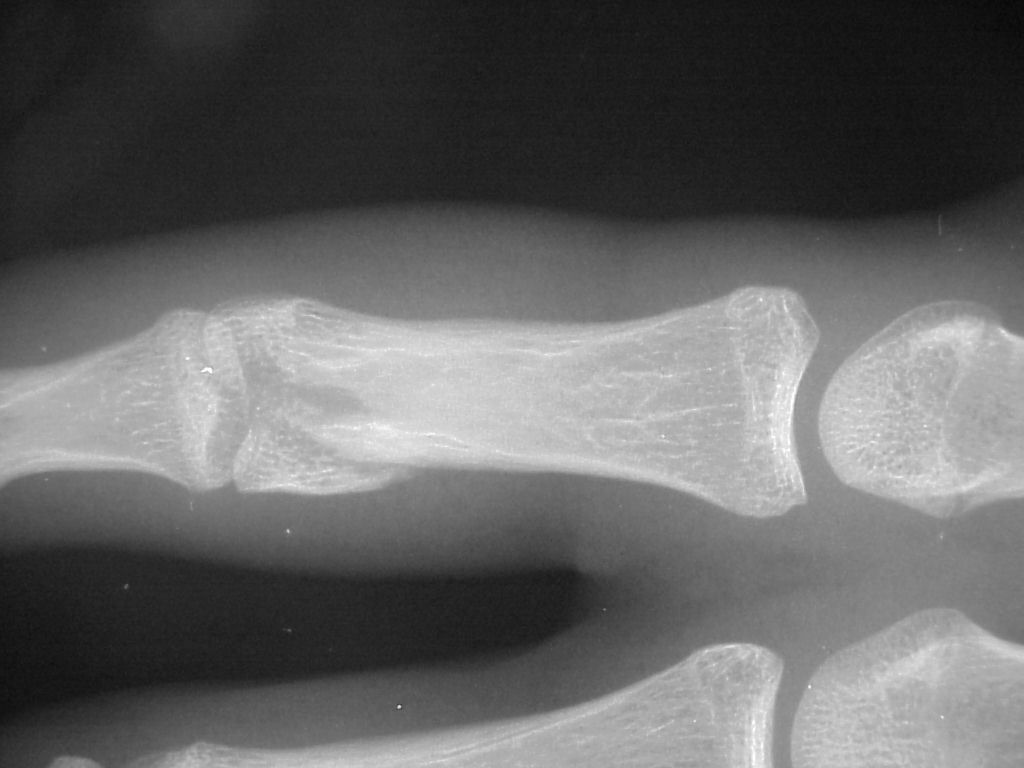

Clinical Example: Unicondylar proximal phalanx head fracture with micro screws

Unicondylar fractures of the phalangeal head are common, frequently unstable and unacceptably displaced. Although some may be treated successfully with percutaneous reduction and fixation, many require open reduction. In these cases, the screws were put right through the collateral ligament and sunk into the cortex. I think the simplest way to do this is to reduce and stabilize with two K wires, then remove the wires and replace with screws, one at a time, so reduction is maintained throughout. 1mm=39/1000" Kwire, so doing the math, here is how you choose the right sized Kwire to use as both drill and provisional fixation:

With two screws, bicortical fixation is not needed. The video below illustrates the steps involved, which are the same with either open or percutaneous fixation.

Click on each image for a larger picture